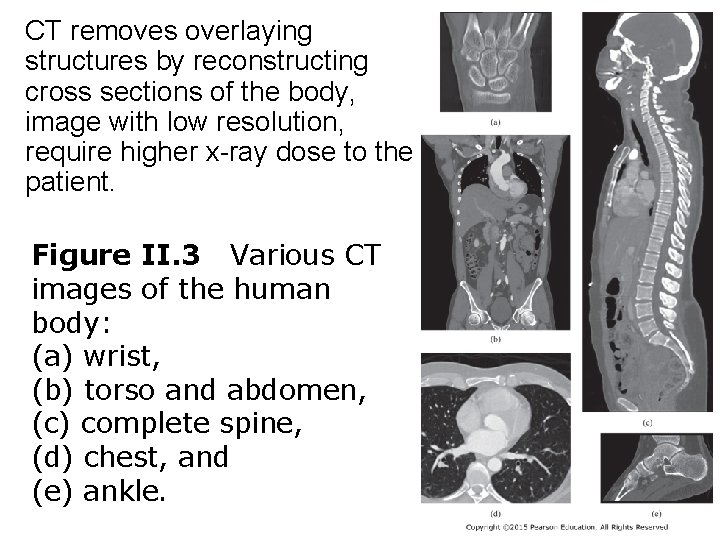

CT removes overlaying structures by reconstructing cross sections of the body, image with low resolution, require higher x-ray dose to the patient. Figure II. 3 Various CT images of the human body: (a) wrist, (b) torso and abdomen, (c) complete spine, (d) chest, and (e) ankle.